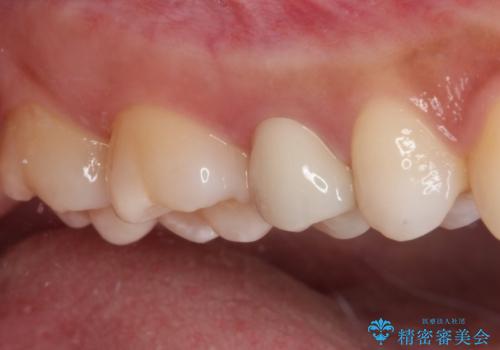

海外転居前にむし歯を治療したい 精密なむし歯治療

- 近々海外へ転居するとのことで、事前に処置をしておくべきむし歯がないか、気にして来院された患者様です。

レントゲン写真などから、速やかに処置を行うべき歯が2歯あったため、それぞれセラミックインレーとPGAインレー(ゴールドインレー)にて修復治療を行うこととしました。

どちらの歯も痛みなどの症状はなく、治療後も異常所見なく経過をたどっています。

上顎大臼歯は向かい合った人から見えることはほとんどないため、切削量が少なく、適合の良いゴールドインレーが大変おすすめとなります。